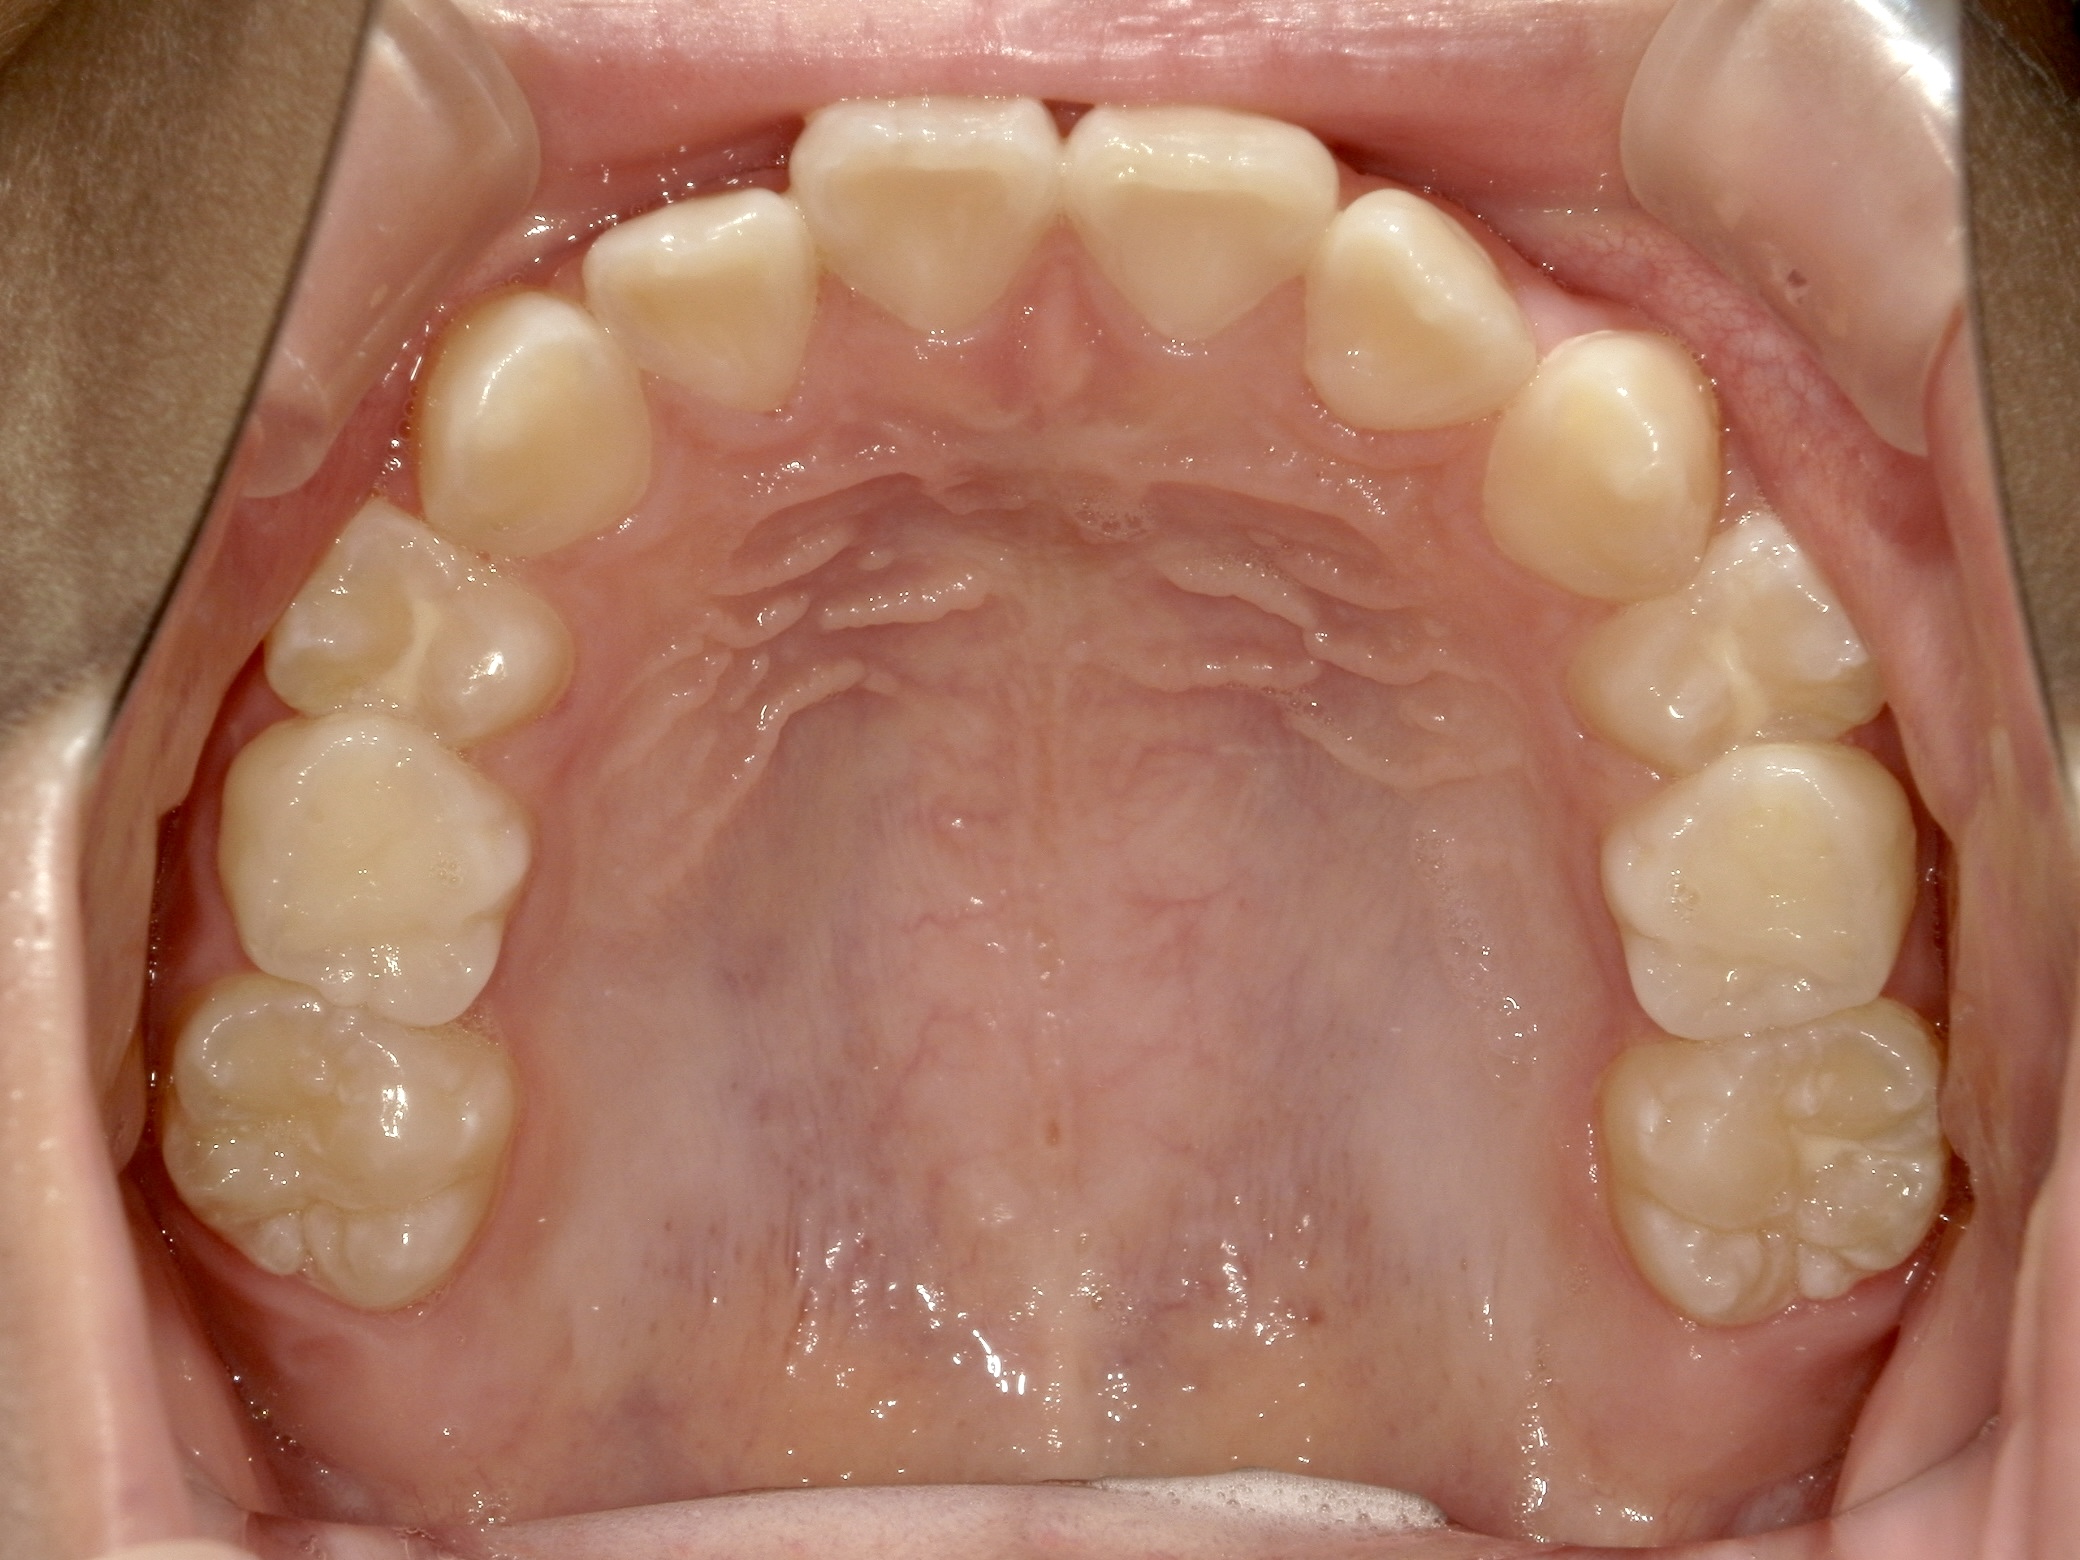

治療中/上の歯だけの状態

出っ歯傾向が改善し、きれいなアーチになっています。 左右ともに奥から2つ目の歯は乳歯で永久歯への生え変わりを待っています。 -